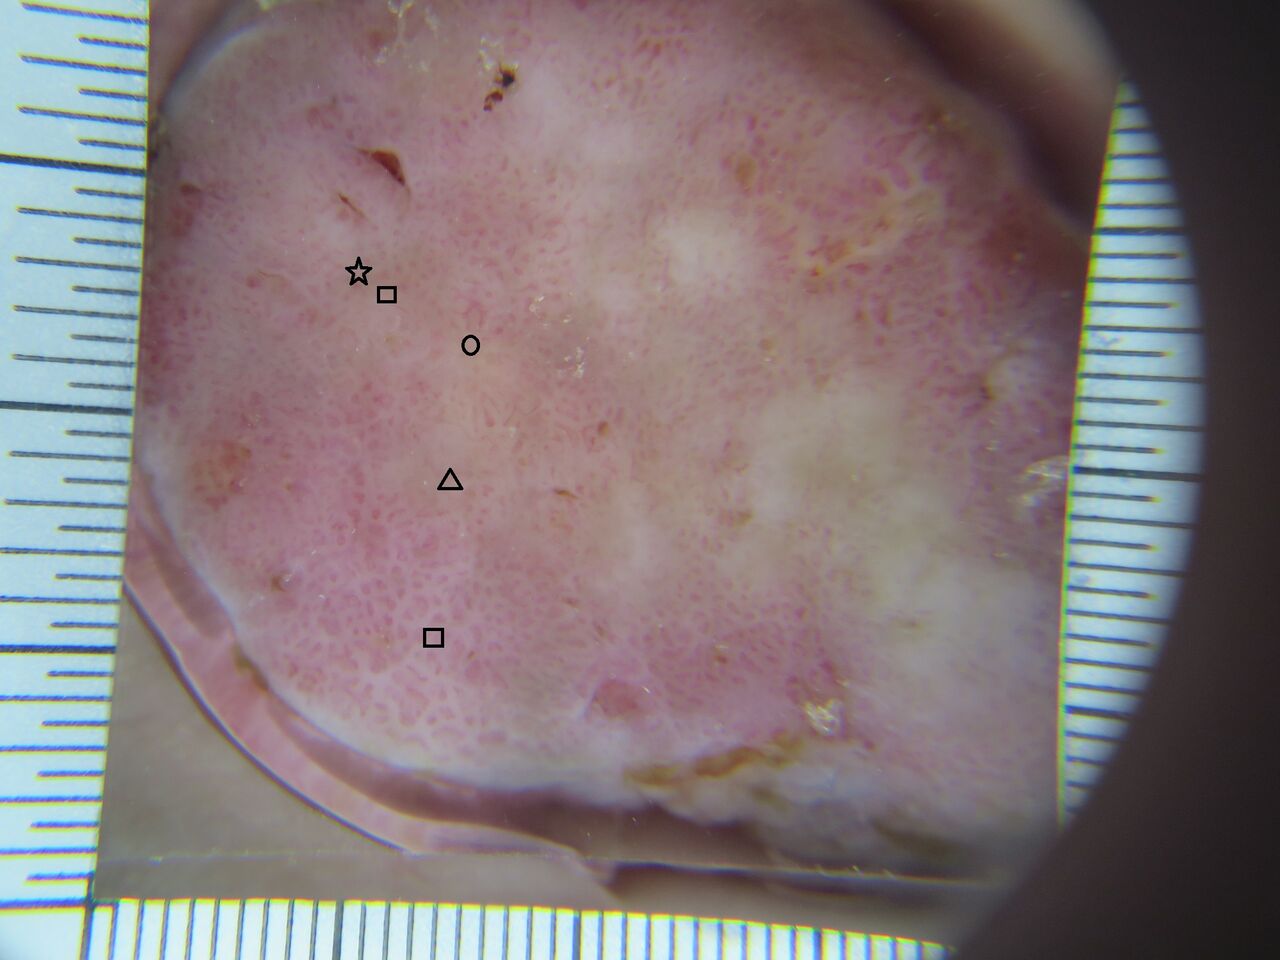

イタリアで開発されたピーリング剤「PRX-T33」を使用したマッサージピールのご案内です。

高濃度トリクロロ酢酸と低濃度過酸化水素とコウジ酸が主成分です。

マッサージピールは、真皮でコラーゲン生成をうながす新しいピーリング施術です。エイジングケアにとても高い効果を発揮します。